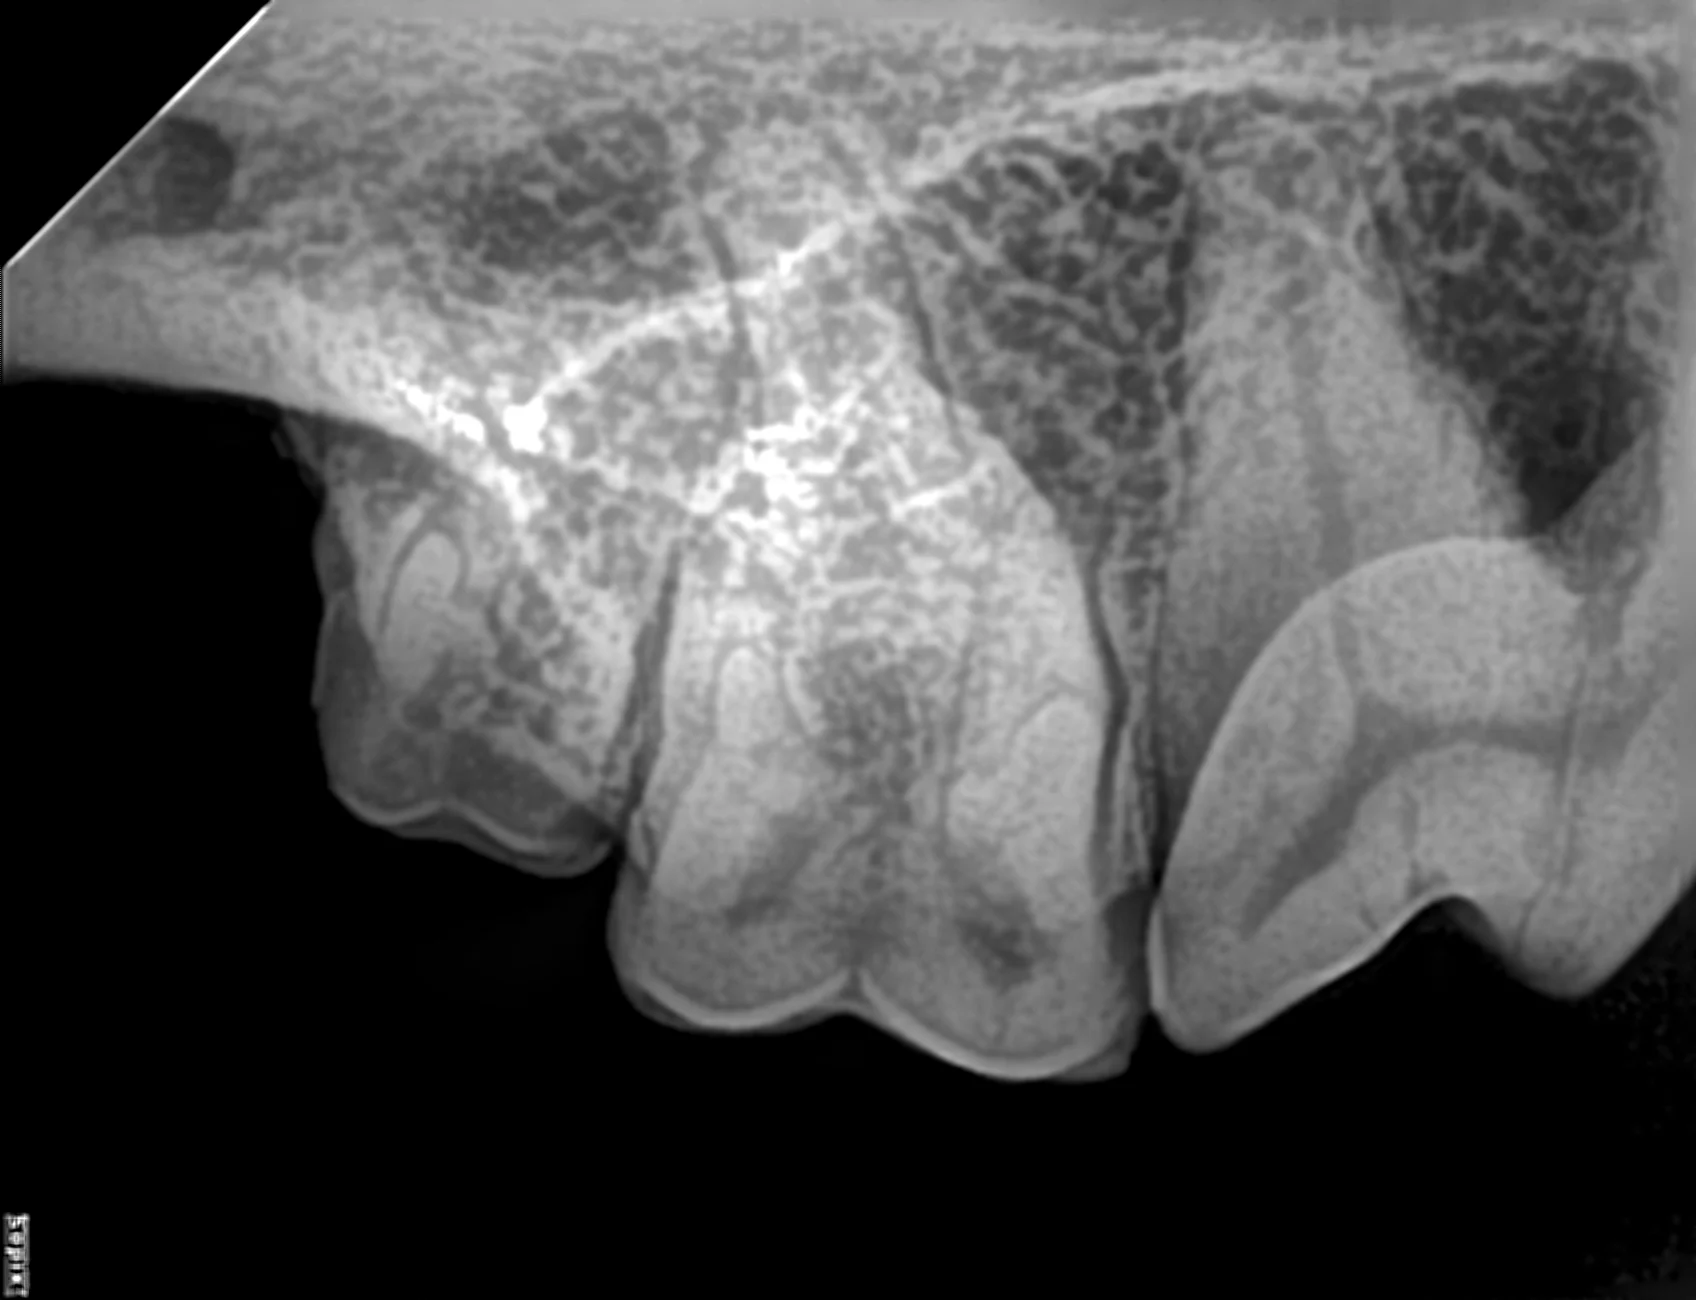

Traditional projections include a combination of intraoral parallel and bisecting angle techniques that are optimal for the largely 2D single- and 2-rooted teeth. For the 3-rooted upper fourth premolar teeth, oblique variants of the intraoral bisecting angle technique can be used to separate mesiobuccal and palatal roots7; however, traditional projections often do not capture detailed information about the buccal roots of the maxillary molar teeth and surrounding tissues in dogs (Figure 1).

Standard intraoral radiograph of right maxillary molar teeth (ie, 110, 109) using the bisecting angle technique. Palatal roots are visible, but buccal roots are hidden under the superimposed image of the crown of each tooth, making assessment of the buccal roots and their bone support difficult.